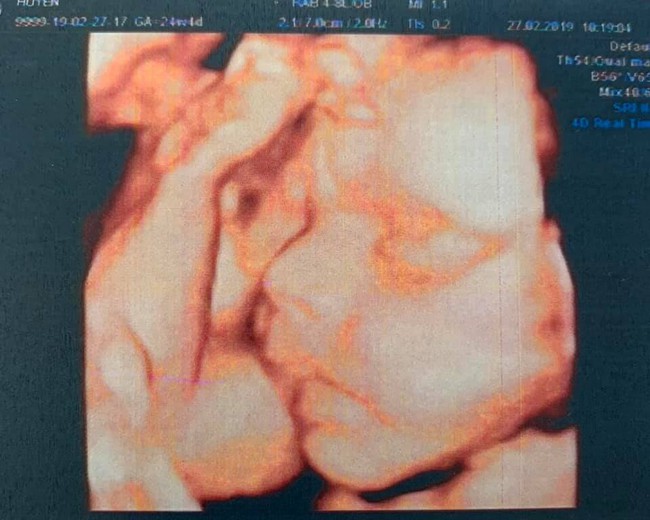

Trên Facebook cá nhân, Hải Băng vừa chia sẻ bức ảnh chụp siêu âm bé thứ ba kèm dòng trạng thái: "Trộm vía lắm em khỏe mẹ cũng ổn định. Bầu 3 đứa đi siêu âm đứa nào mũi cũng cao, mà đẻ ra thì đứa nào cũng tẹt, không giống hai ông bà già nhà nó gì hết". Ngoài ra, ở phần bình luận bài đăng, Hải Băng còn tiết lộ với một người bạn rằng cô sẽ sinh bé vào cuối tháng 5 tới.

Ảnh siêu âm con thứ ba được Hải Băng đăng tải lên trang cá nhân.